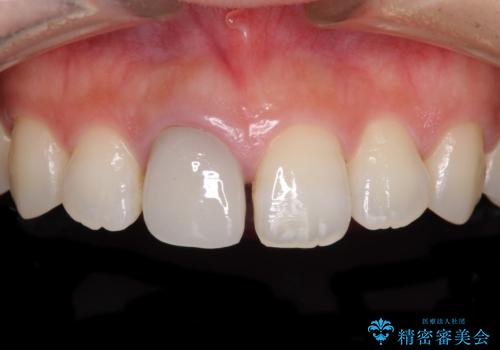

- 近医にて被せた前歯のクラウンの色の違いを気にして来院された患者様です。

オーダーメイドのオールセラミッククラウンにて補綴することとしました。

元々すきっ歯であったため、隙間を全て埋めると左右で大きさがアンバランスとなることが懸念されました。

違和感のない程度に隙間を小さくして、自然な見た目に仕上げました。